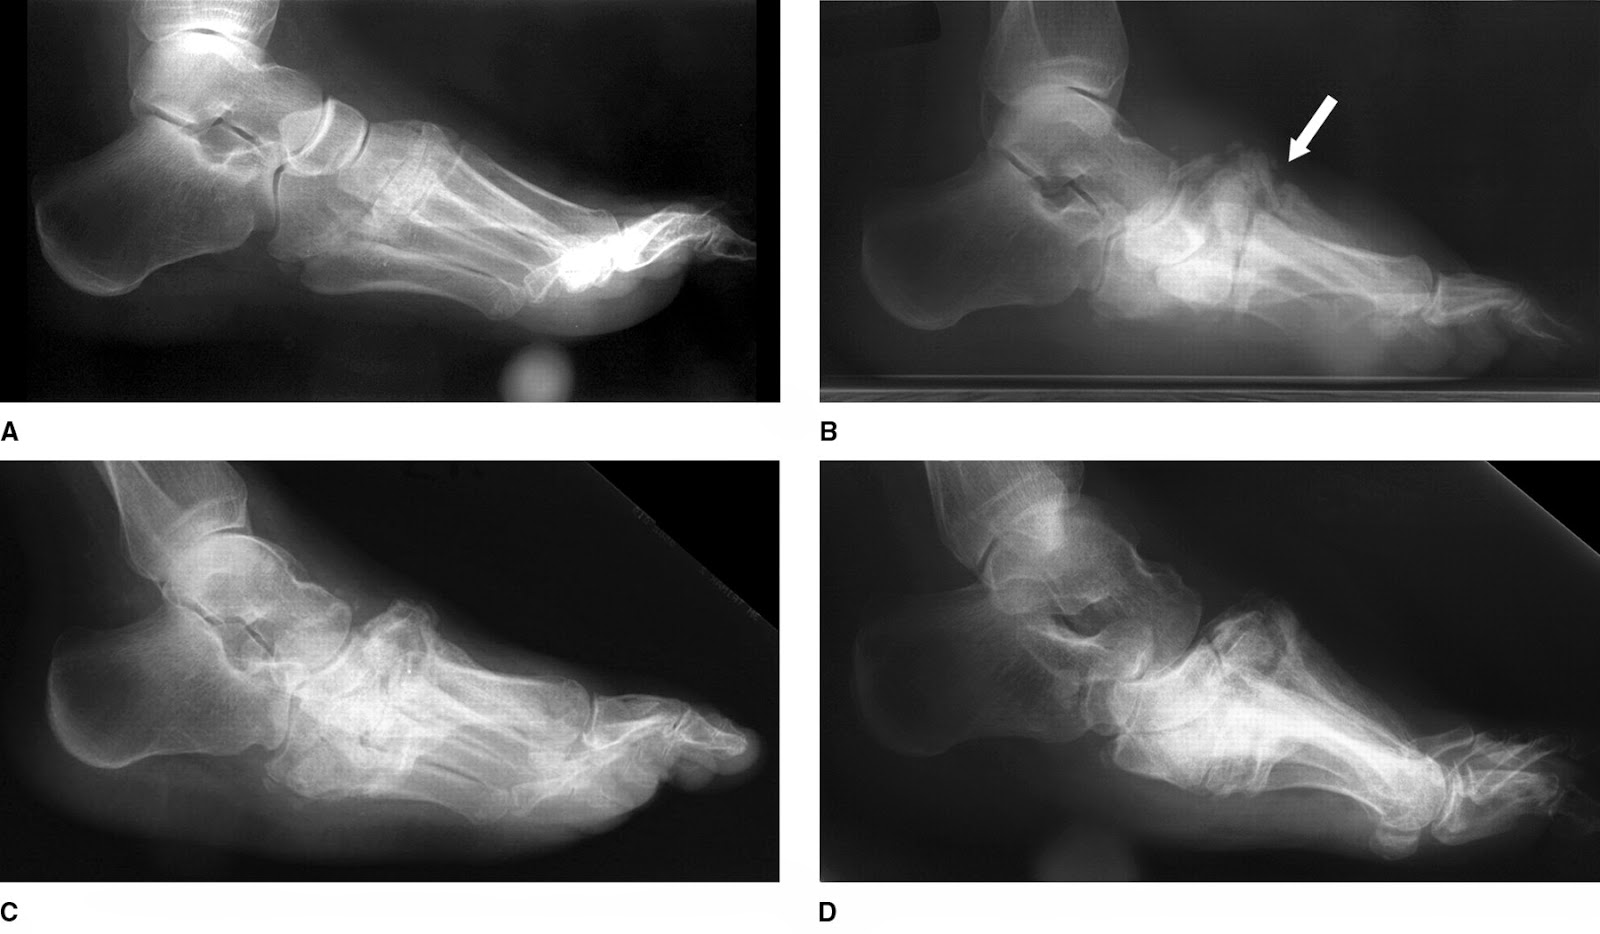

The Charcot foot a pictorial review Insights into Imaging Full Text Nuclear medicine Can Charcot Foot Come Back Who will look after my foot?. Early diagnosis is critical for avoiding surgery, including amputation. Charcot foot ranges in severity, and damage can be permanent. There’s no specific cause for charcot foot. The chronic charcot foot — a ‘rocker bottom’ foot caused by dislocation and fracture of the bones in the midfoot. But some things can trigger it: Charcot foot. Can Charcot Foot Come Back.

Can Charcot Foot Come Back . There’s no specific cause for charcot foot. For those with an active charcot foot, this means that fractures and dislocations can occur without a whisper of pain, silently and progressively altering the foot and ankle. Your foot may become deformed if you do not get appropriate treatment early enough and you. Can develop charcot foot in both feet. Charcot foot ranges in severity, and damage can be permanent. Early diagnosis is critical for avoiding surgery, including amputation. This condition is also called charcot neuroarthropathy, charcot arthropathy, or diabetic foot. But some things can trigger it: Charcot foot is a condition that can develop from peripheral neuropathy caused by diabetes. Charcot foot, a serious complication of diabetes, is a condition that affects the bones, joints, and soft tissues of the foot. Who will look after my foot?. The chronic charcot foot — a ‘rocker bottom’ foot caused by dislocation and fracture of the bones in the midfoot. A sprain or broken bone that doesn’t get.

Can Charcot Foot Come Back There’s no specific cause for charcot foot. There’s no specific cause for charcot foot. For those with an active charcot foot, this means that fractures and dislocations can occur without a whisper of pain, silently and progressively altering the foot and ankle. This condition is also called charcot neuroarthropathy, charcot arthropathy, or diabetic foot. Charcot foot ranges in severity, and damage can be permanent. Early diagnosis is critical for avoiding surgery, including amputation. Charcot foot, a serious complication of diabetes, is a condition that affects the bones, joints, and soft tissues of the foot. Charcot foot is a condition that can develop from peripheral neuropathy caused by diabetes. Your foot may become deformed if you do not get appropriate treatment early enough and you. Who will look after my foot?. The chronic charcot foot — a ‘rocker bottom’ foot caused by dislocation and fracture of the bones in the midfoot. A sprain or broken bone that doesn’t get. But some things can trigger it: Can develop charcot foot in both feet.